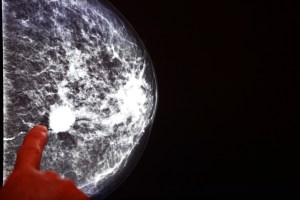

Breast cancer is one of the most common cancers, and if caught early, is highly treatable. In fact, the majority of deaths from breast cancer occur because the disease has been caught too late, having already spread to other parts of the body, a process called ‘metastasis.’ Recently, scientists discovered that women who have a heightened number of a particular type of immune cells, called ‘neutrophils,’ in their blood stream have a higher chance of their breast cancer metastasizing to other tissues. But they couldn’t figure out why.